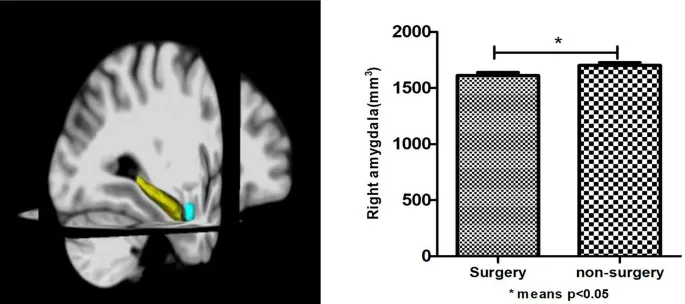

В когорте 2 мы обнаружили, что пожилые люди с историей операции с общей анестезией имели более низкие баллы по Монреальской шкале оценки когнитивных функций (MoCA) и меньший объем правой миндалины (p < 0,05). Не было существенной разницы (p > 0,05) в образовании, употреблении алкоголя, гипертонии и диабете между двумя группами. Таблица 1 показывает результаты.

Чтобы объяснить возможные механизмы, с помощью которых операция с общей анестезией влияет на cognition, мы добавили данные структурной магнитно-резонансной томографии. На основании того, была ли у них история операции с общей анестезией, эти 194 человека были разделены на группу операции (n = 92) и группу без операции (n = 102) (Таблица 3). Мы в конечном итоге обнаружили, что пожилые люди с историей операции с общей анестезией имели более низкие баллы MoCA и меньший объем правой миндалины (p < 0,05) (Рис. 2). С помощью корреляционного анализа мы обнаружили, что объем правой миндалины был значимо коррелирован (p = 0,003, r = 0,212) с MoCA. Затем с помощью линейного регрессионного анализа (модель посредничества) мы обнаружили, что операция с общей анестезией напрямую влияла на оценку MoCA, влияя на объем правой миндалины (B = 1,315, p = 0,036 95% ДИ 0,088–2,542) (Рис. 3).

Чтобы further explore (дальше исследовать) возможные механизмы, с помощью которых операция с общей анестезией влияет на когнитивные функции, мы затем включили данные магнитно-резонансной томографии. Основываясь на нашем предыдущем исследовании, мы все еще mainly focused (в основном сосредоточились) на effects (влиянии) миндалины на когнитивную функцию. Используя данные 194 пожилых людей, подобранных по возрасту, полу и образованию, мы обнаружили, что пожилые люди с историей общей анестезии имели меньший объем правой миндалины и худшие баллы MoCA. Через correlation analysis (корреляционный анализ) мы обнаружили, что объем правой миндалины положительно коррелировал с общим баллом MoCA. Затем, с помощью linear regression analysis (линейного регрессионного анализа) (mediation model - модель посредничества), мы обнаружили, что операция с общей анестезией напрямую влияла на оценку MoCA, влияя на объем правой миндалины. В предыдущих когнитивных исследованиях MoCA обычно используется как screening tool (скрининговый инструмент) для общей когнитивной функции, и оценка обычно отражает overall cognitive level (общий когнитивный уровень) человека. Основываясь на наших результатах и статистическом анализе, можно сделать вывод, что может существовать связь между общей анестезией, миндалиной и общей когнитивной функцией, однако вышеуказанные выводы все еще need to be further verified (нуждаются в дальнейшей проверке) лонгитюдными исследованиями.